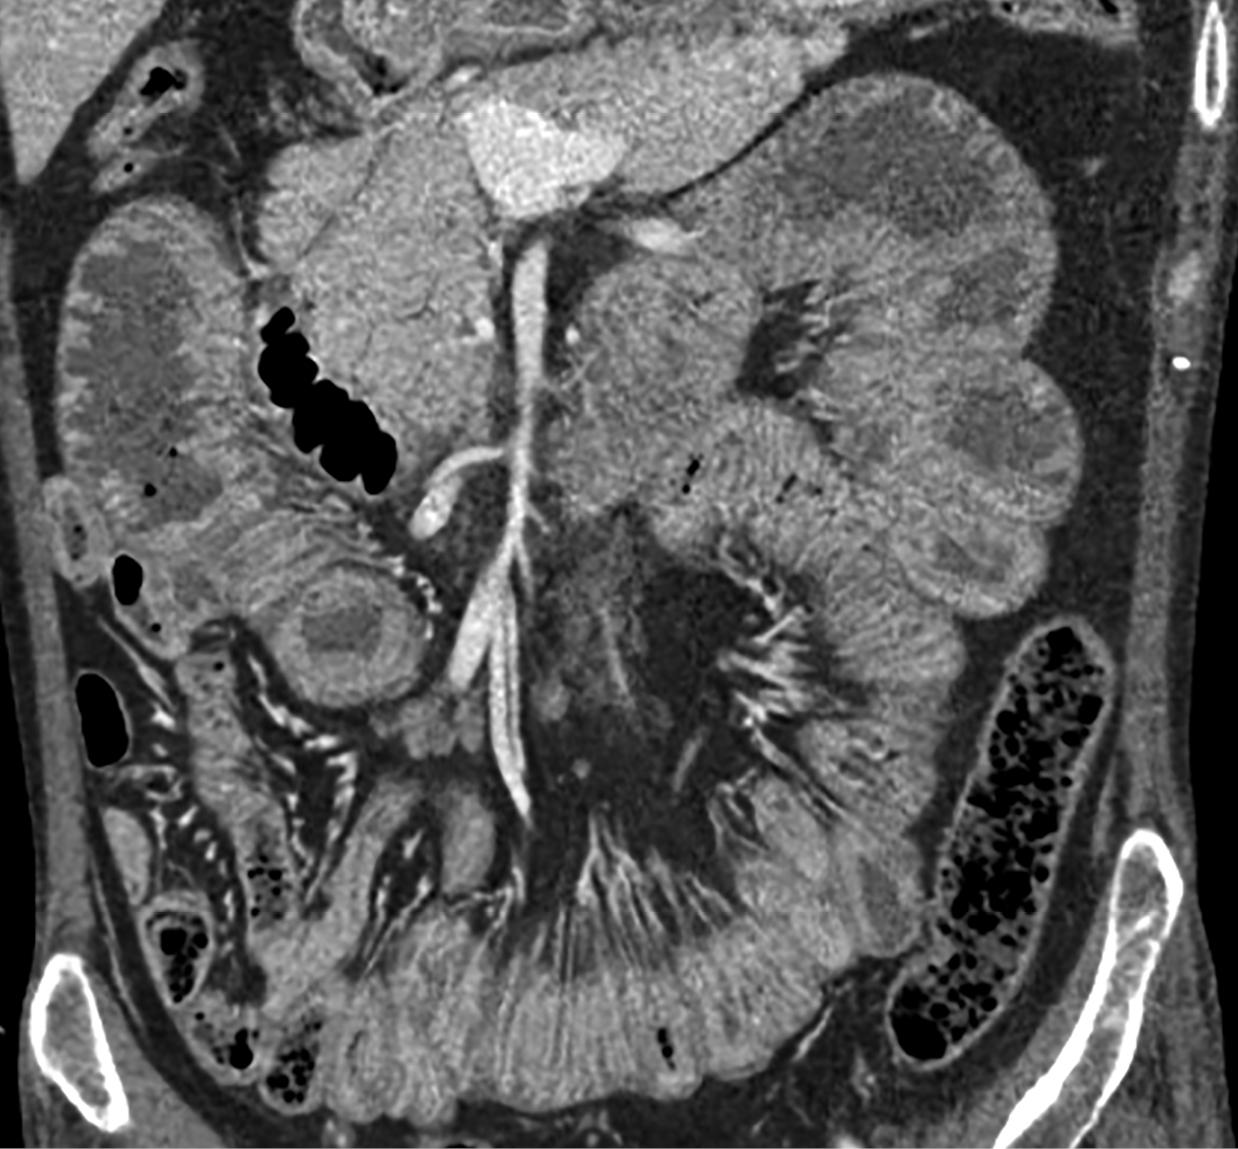

Локальное уплотнение легочной ткани было расценено либо как метастаз опухоли ЩЖ, либо как первичная опухоль легкого. При КТ брюшной полости новообразований не выявлено. Визуализированы признаки пареза кишечника (рис. 4), диффузная гиперплазия обоих надпочечников — толщина правого увеличена до 1,4 см, левого — до 1,6 см (рис. 5). При КТ головного мозга выявлены признаки выраженной атрофии коркового вещества. Область турецкого седла не изменена.

Рисунок 4. КТ брюшной полости: парез кишечника.

Рисунок 5. КТ брюшной полости: диффузно-гиперплазированные надпочечники: правый — до 1,4 см, левый до — 1,6 см.